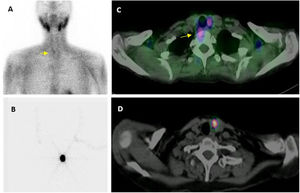

Preoperative image.

Localization with MIBI: planar image (A) showing a small lower right adenoma (arrow), which the SPECT/CT fusion image (C) confirms and locates in an ectopic situation (right pre-vertebral).

Preoperative localization of left lower parathyroid adenoma with the ROLL technique: planar (B) and transaxial SPECT/CT images (D) after the intralesional administration of MAA.